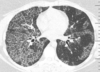

HOMEM, 50 ANOS, INTERNADO POR DISPNEIA + HEMOPTISE DE INÍCIO SÚBITO

áreas de opacidade em vidro fosco associadas a espessamento de septos interlobulares e intralobulares

HEMORRAGIA PULMONAR